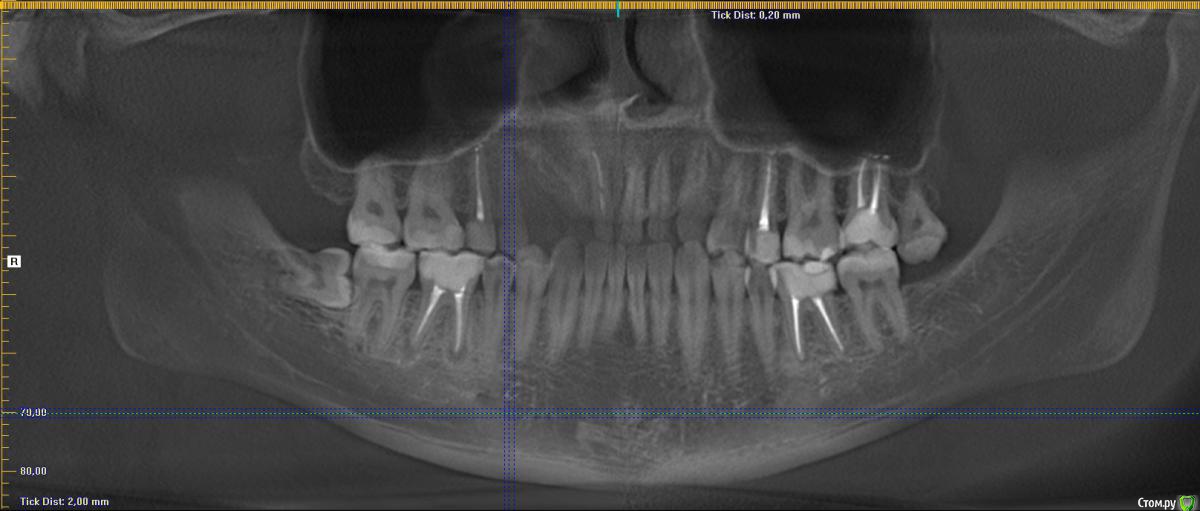

Добрый день! На протяжении нескольких лет обращался на профилактические осмоты - всегда говорили что Ок.

кто говорил, что 8ку удалять. А сходил к хирургу - сказал что все уже вырасло и раз не беспокоит - можно не трогать. Показаний нет.

В сейчас, опять сделали снимок и говорят, что на соседнем зубе кариес, причем значительный - и скорее всего нужно удалять нервы на 7ке, после удаления 8ки. Обращался по страховке.

Снимок не дали, но есть 2х летней давности. Есть ли здесь кариес или это просто тень от 8ки?

удаление 48,28

15,25,27,36 протезирование коронками

46 - повторное лечение и протезирование

А на 47 видно следы кариеса?

Есть какая-то зона деминерализации. Лучше свежий снимок сделать.